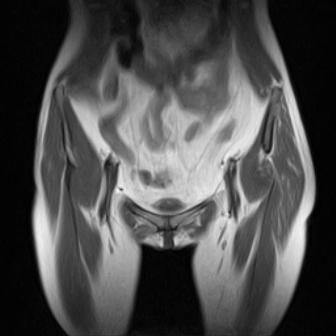

请看看我的片子,我得的什么病,该怎么治疗?谢谢[img][/img]

片子不全,应该是左侧股骨头无菌坏死,右侧似乎没问题,到正规医院治疗,千万别看广告去小医院,吃中药什么的,都是骗人的(说了也白说,百分百都得让人骗点钱才甘心。)

应该是左侧股骨头无菌坏死